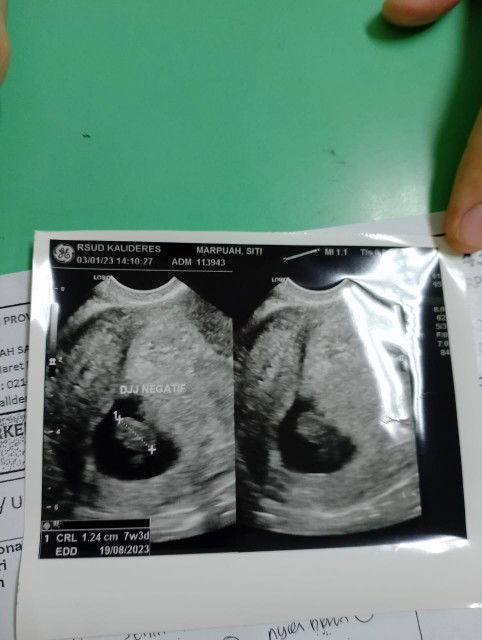

Ddj tidak terdeteksi

Wajar ga si bun usia 7 minggu ddj tdk terdeteksi (di nyatakan meninggal ) sma dokter 😥